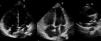

A 70-year-old woman with a permanent VVI pacemaker implanted two years previously for advanced atrioventricular block came to our emergency department due to chest pain, dyspnea and palpitations for the past two hours. An electrocardiogram performed at that time showed atrial fibrillation at 140 bpm. After electrical cardioversion, the electrocardiogram during ventricular pacing showed a right bundle branch block pattern (Figure 1). No chest X-ray was performed at that time, but a previous one was investigated (Figure 2). A transthoracic echocardiogram (Figure 3) suggested malposition of the pacemaker lead in the left ventricle with right atrial and ventricular dilatation, so a three-dimensional transesophageal echocardiogram (Figure 4) was obtained that showed the pacemaker lead passing through a 2-cm interatrial communication and the mitral valve, and finally into the left ventricle.

This complication should be considered when right bundle branch block is seen on a pacing electrocardiogram and the pacemaker lead has a posterior position on the lateral chest X-ray. A definitive diagnosis is obtained by echocardiography.

In asymptomatic patients, long-term anticoagulation therapy is preferred but in this case, with a symptomatic interatrial communication, we decided on surgical retraction of the lead and permanent closure of the septal defect.